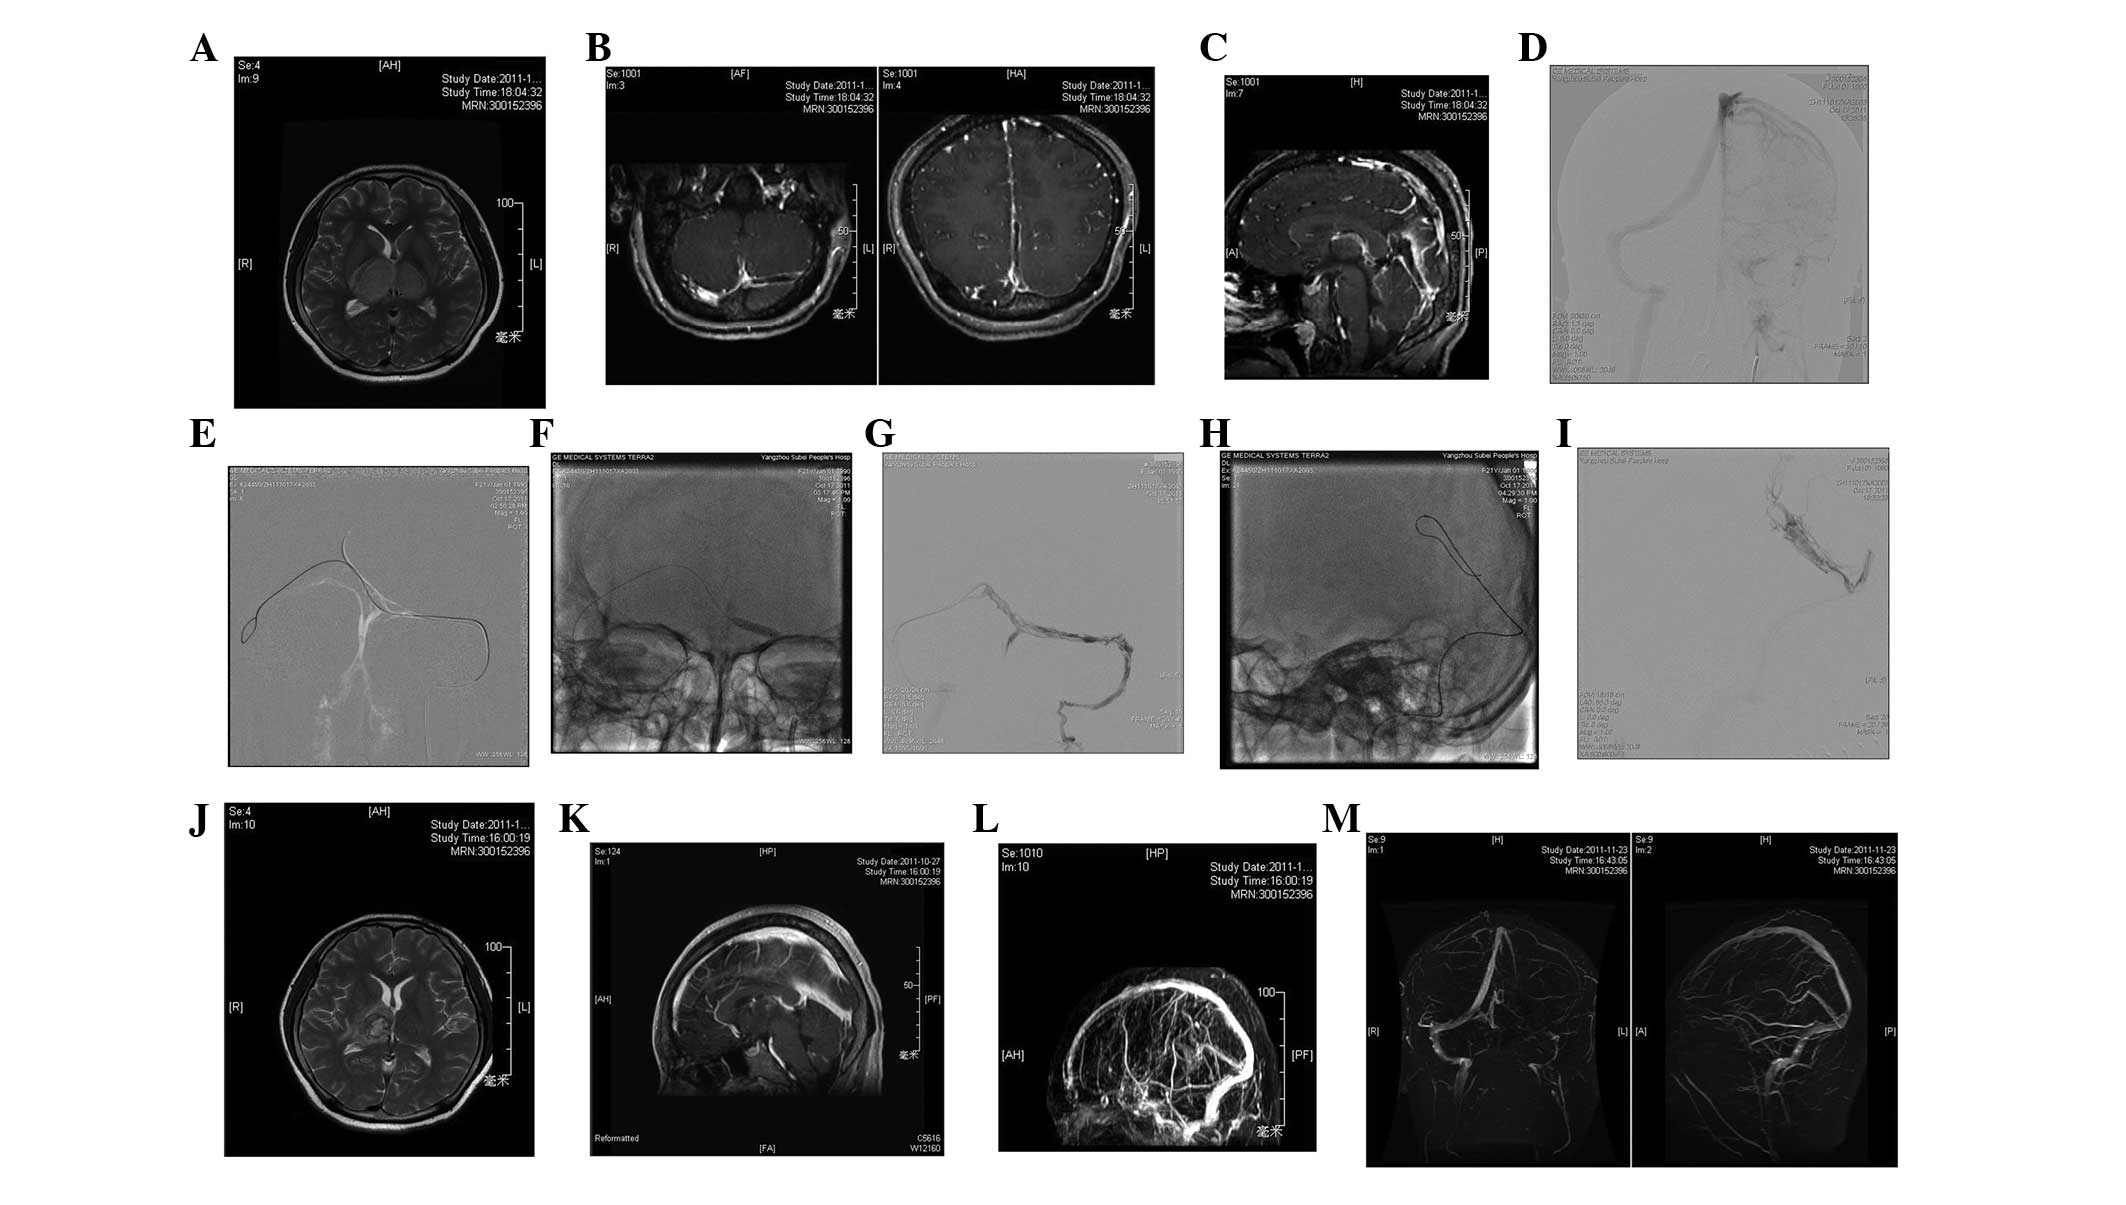

Typical case 1 (female, 47 years-old)

Sudden headache and vomiting occurred 2 days prior to hospitalization. Heparinization was performed following admission. However, the disease was progressively aggravated. Minor epilepsy was observed three times and the GCS score was 9. CT examination revealed that the left parietal lobe was infarcted and hemorrhage was identified at the junction of the right temporal and occipital lobes (Fig. 1A and B). MRI revealed that thrombi existed in the superior sagittal sinus and straight sinus (Fig. 1C). In addition, DSA showed that the superior sagittal sinus and straight sinus was not phanerous due to thrombosis or congenital dysplasia. The cortical veins were connected to the sigmoid sinus through the sylvian vein, cavernous sinus, pterygoid plexus and vein of Labbé (Fig. 1D). The sacculus expanded during surgery (Fig. 1E). The microcatheter was left in the superior sagittal sinus for 3 days after surgery. On day 2 following surgery, the awareness of the patient improved significantly, simple verbal exchanges became possible and right side muscle strength was at level 3, according to the Oxford Scale. On day 8 following surgery, the patient was conscious, speech was fluent and muscle strength was at level 5. DSA revealed that the superior sagittal sinus, straight sinus and left transverse sinus were well-developed at day 11 following surgery (Fig. 1F). After one year, the patient exhibited no neurological deficit and MRV demonstrated that the superior sagittal sinus and straight sinus had recovered well (Fig. 1G).

Figure 1

Catheter-directed thrombolysis in the superior sagittal sinus. (A) Intracranial left parietal lobe infarction shown by CT; (B) hemorrhage at the junction of the right temporal and occipital lobes; (C) thrombosis of the superior sagittal sinus and straight sinus shown by enhanced MRI; (D) DSA showed that the superior sagittal sinus and straight sinus did not develop; (E) sacculus expanded during surgery; (F) on day 11 following surgery, review with DSA showed that the superior sagittal sinus, straight sinus and left transverse sinus developed well; (G) one year later, review with MRV showed that the superior sagittal sinus, straight sinus and left transverse sinus developed well. CT, computed tomography; MRI, magnetic resonance imaging; DSA, digital subtraction angiography; MRV, magnetic resonance venography.